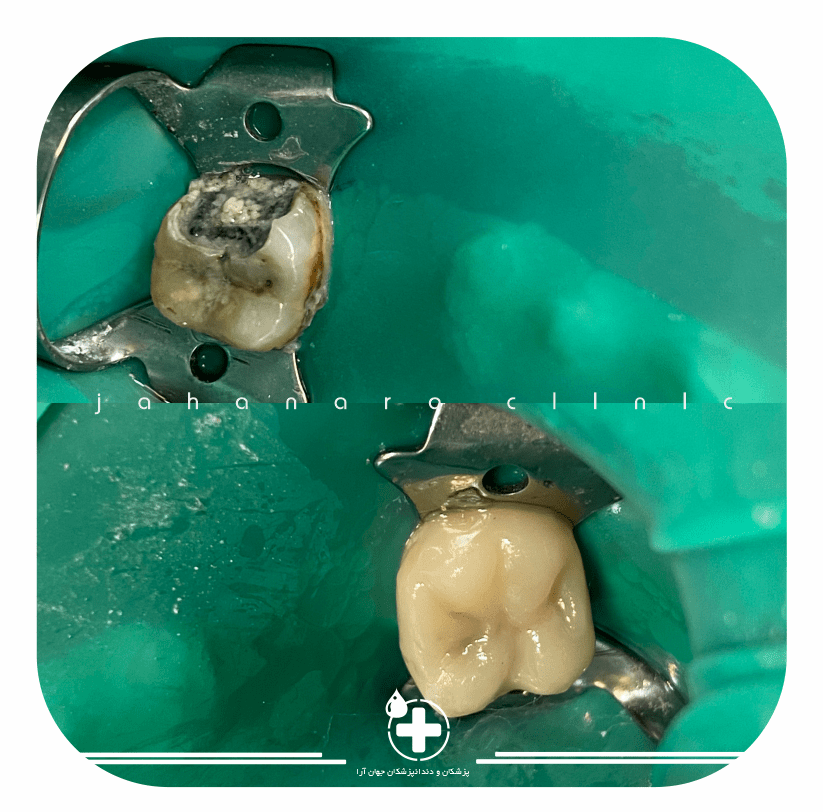

ترمیم همرنگ

ترمیم پوسیدگی همرنگ دندانقیافش مثل روز اول میشه

عصبکشی روتاری

عصب کشی با سیستم مدرن روتاریبالاترین سرعت و کمترین مشکلات